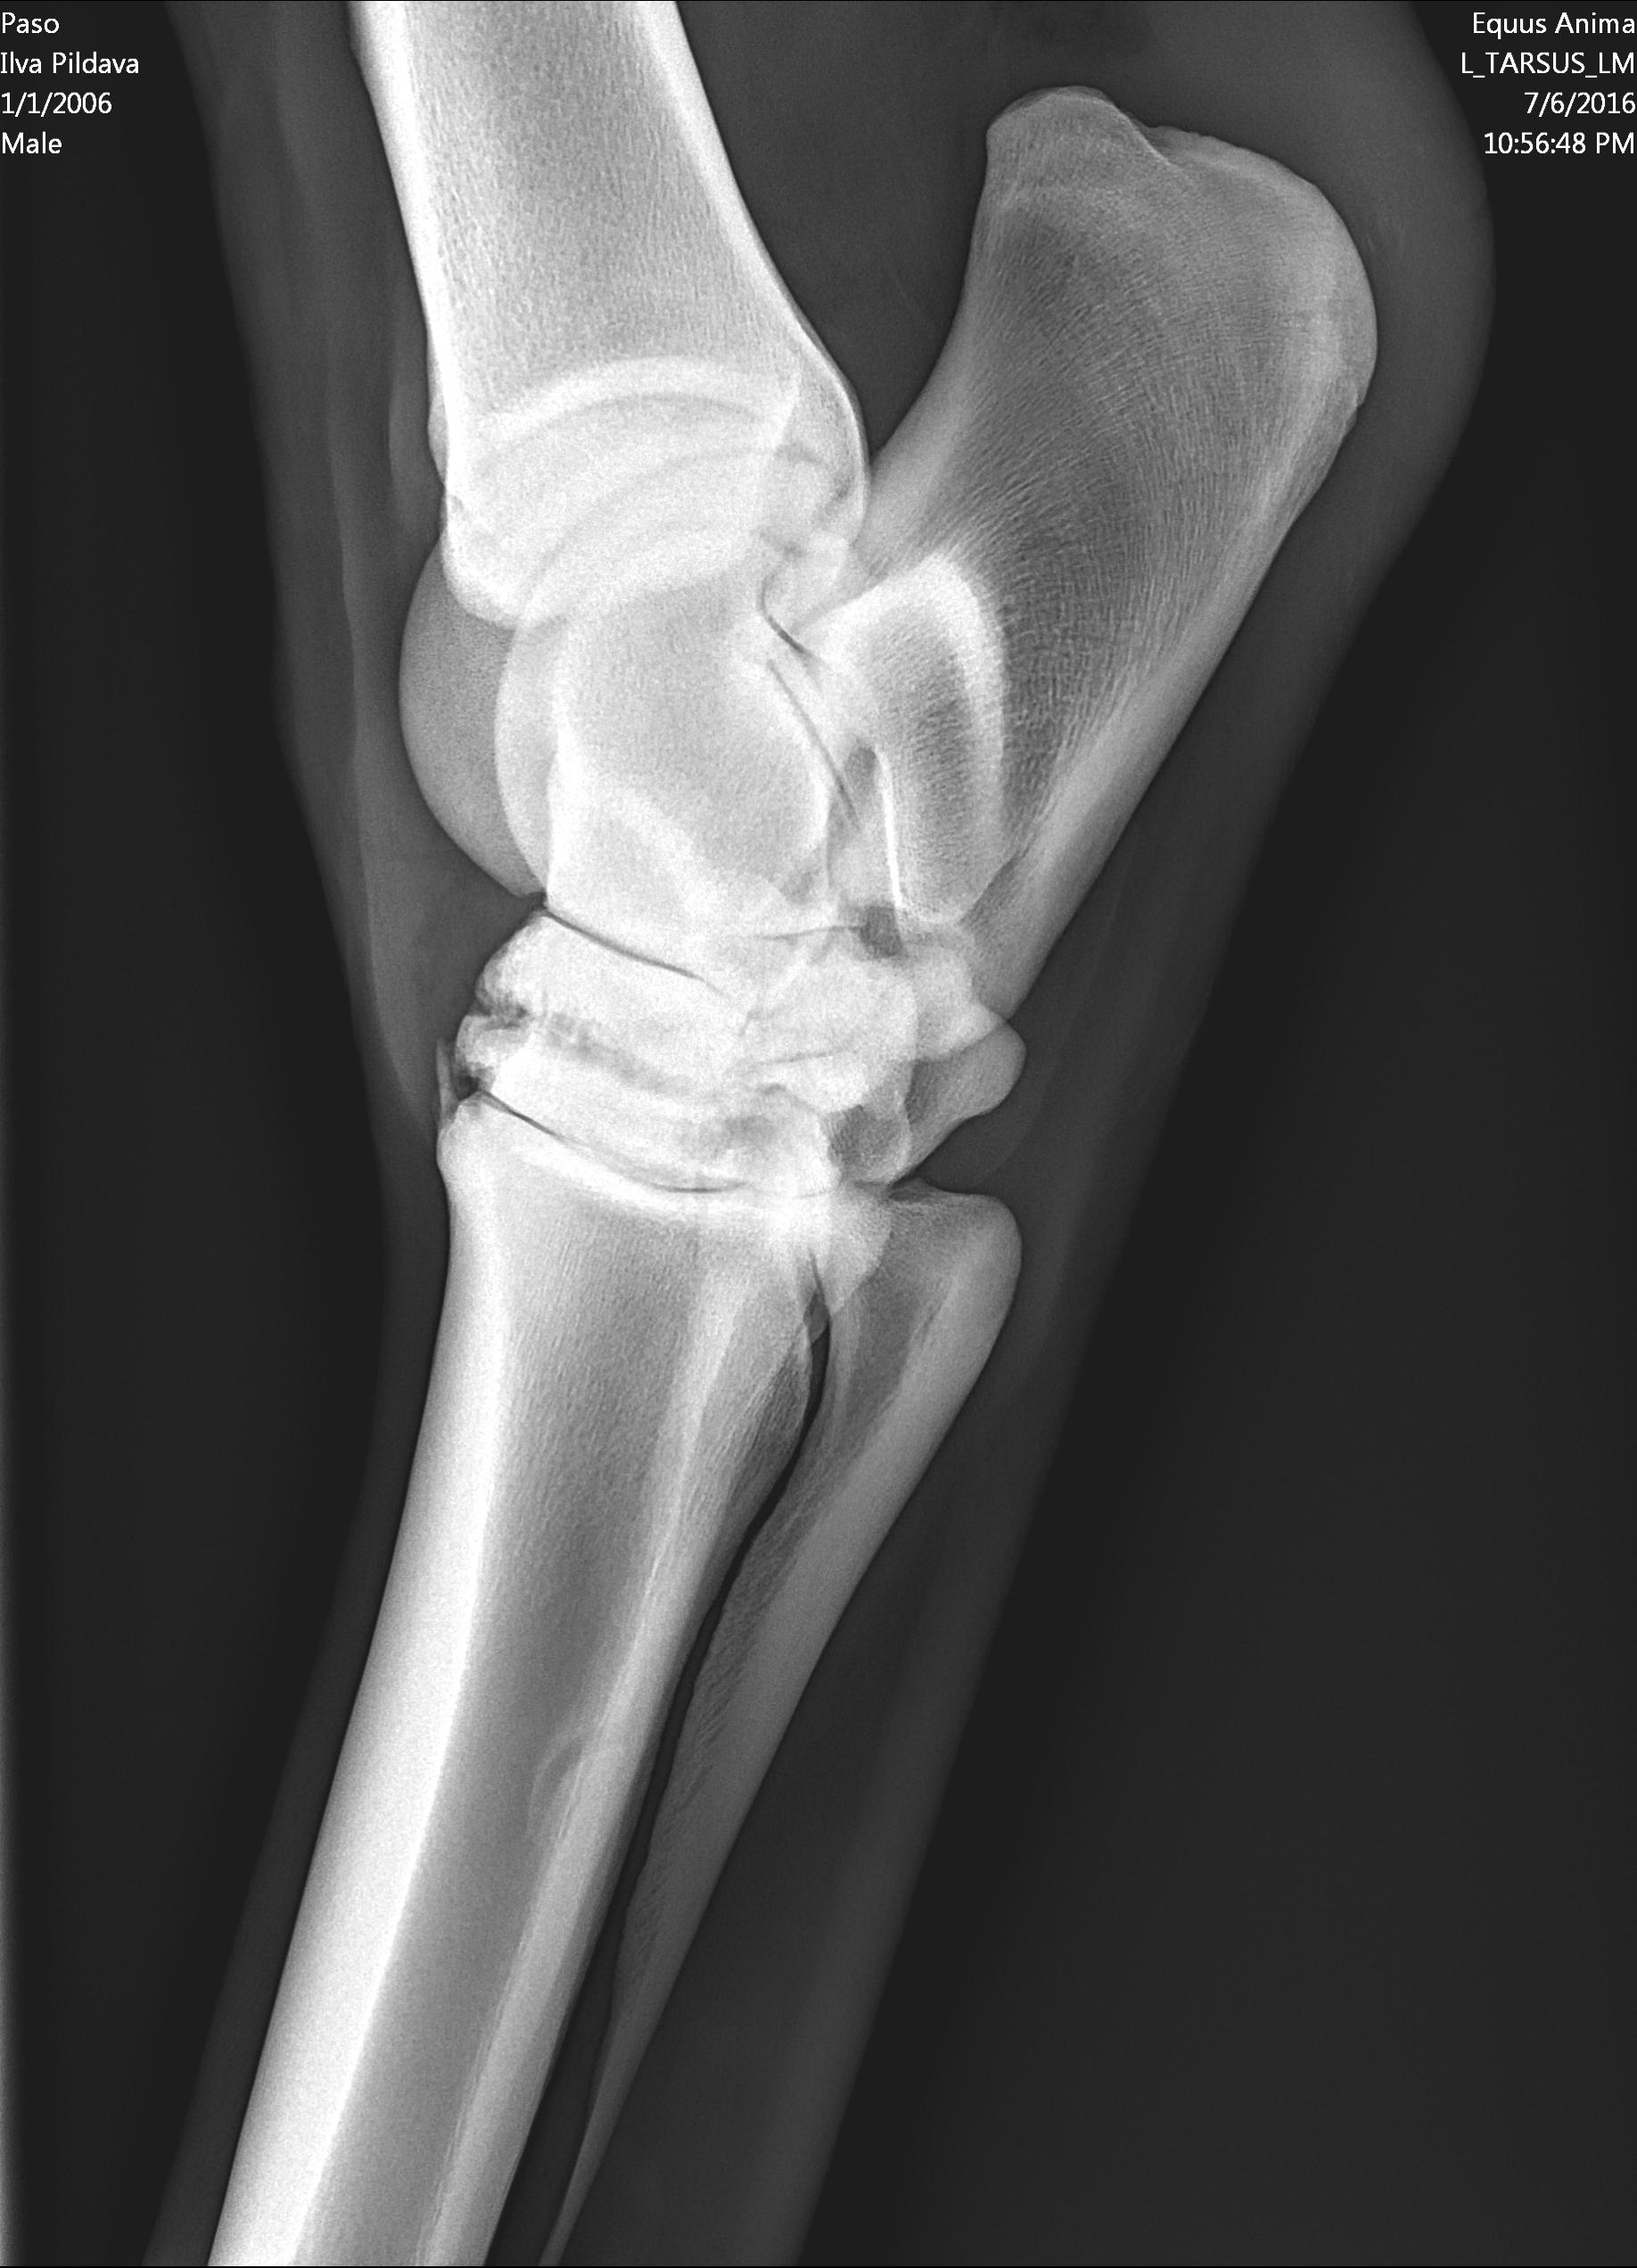

U majei loshadi ( 10 let) kastrat, v proslom godu obnaruzili spat I sdelali kurss Tildren, 16.10.2017. ehso odin kurss, daju polgoda eto http://ru.eggersmann.info/432_/132_Profi_Gelenk_aktiv.html, I vot kakije u loshadi rentgeni po datam. Prigaju do 110 cm, edu na sorevnavanije, idjot on horosho. esli stojal v bokse , snachala hromaet,no potom 2-4 minuti v risi i prohodit. Ja bi hotela prigatj vishe,no bojus ,mozno li. Letom dva raza bila ,chto v trenirovke zahramal ochen silno,no cerez paru chasov ,vsjo proslo.